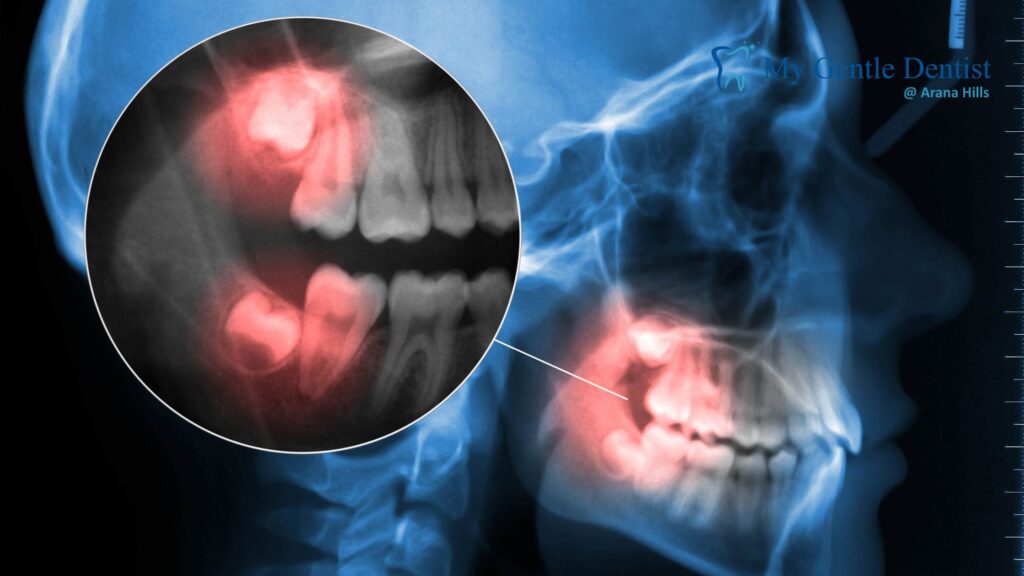

Wisdom tooth pain often occurs when the third molars (wisdom teeth) emerge incorrectly or become impacted. This can place pressure on surrounding jaw structures, muscles, and nerves, leading to stiffness, swelling, and reduced mobility.

- Impacted wisdom teeth trapped beneath the gum or bone

- ✅ Digital X-rays and 3D scans to assess impaction or misalignment